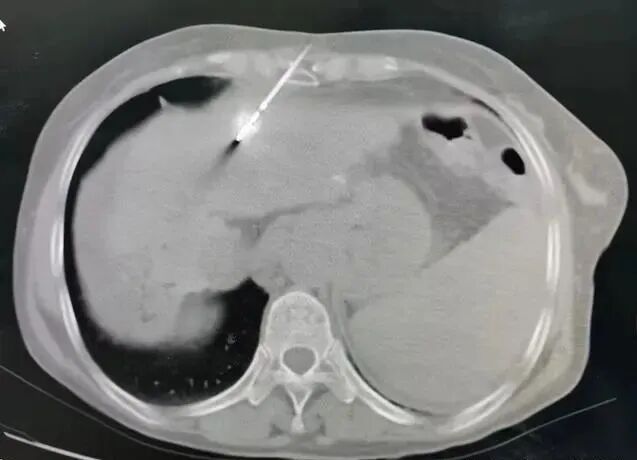

道理很简单,肿瘤要从体内某个地方取到身体外面来,要经过皮下组织、皮肤,只要有癌细胞在这个路程中掉出来,在路上增殖、生长,那就形成了人为的种植、转移。根据2000年以前的文献,国内外有很多医生报道了他们经历的针道转移的病案。1991年Smith报道针道转移的几率是 0.003%-0.009%,发生比例非常的低,但是这位医生将很多良性肿瘤也统计了出来。国内很多医生报道的比例大很多,有的高达2.3%。2、穿刺出血可能将一部分肿瘤细胞"冲入"穿刺针道内;4、肿瘤位于包膜下,比如肝癌包膜下肿瘤,刺破肿瘤后,肿瘤细胞会直接溢出生长,造成扩散转移;据报道:细针穿刺可引起大约0.006%的种植,在动物实验中,穿刺实体瘤大约可引起10个肿瘤细胞的种植;并可导致85%的种植性生长。粗针穿刺虽可增加活检的准确性,但可增加肿瘤种植的发生。1、比如一个肝脏占位,有乙肝、肝硬化,甲胎蛋白AFP升高,CT和磁共振都提示原发性肝癌,还有必要做吗?答:建议不做了!能手术直接手术!为啥呢?已经符合临床肝癌的诊断了,还做它干嘛?2、比如一个乳腺包块,B超和磁共振提示乳腺癌,该不该做?乳腺癌有很多种类型,治疗的方案很多很多种,即使是癌了,根据免疫分型,有的需要先化疗放疗再手术,有的需要先手术再化疗,即使化疗都有很多种方案,还有很多种靶向治疗方案。这些都需要取出肿瘤组织,进行常规病理检查、免疫组化检查或基因检测。所以该做不该做,听专业医生的意见即可。担心转移也要做!答:因为甲状腺切了就没了,很多需要终身服药。如果不穿刺活检,直接切了,最后是良性的,那就后悔大了。但是有些穿刺活检,并不是100%的准确;有的即使穿刺了,还是不能确定是不是恶性的。总的来说,穿刺活检在临床上发挥着不可替代的作用。希望患友们不要畏惧治疗,也不能过度治疗,具体能否进行穿刺活检需要主诊医生结合患者的实际病情进行判断,不能一概而论。推荐阅读